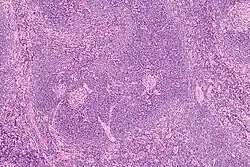

L'histologie (biopsie ostéomédullaire) montre des lésions qui peuvent orienter le diagnostic, associant une hyperplasie lymphatique et vasculaire, une plasmocytose, des atypies sur les mégacaryocytes, une fibrose. Toutefois, ces constatations ne sont pas spécifiques[12] et les données histologiques ne permettent pas d'orienter le traitement médicamenteux[13].